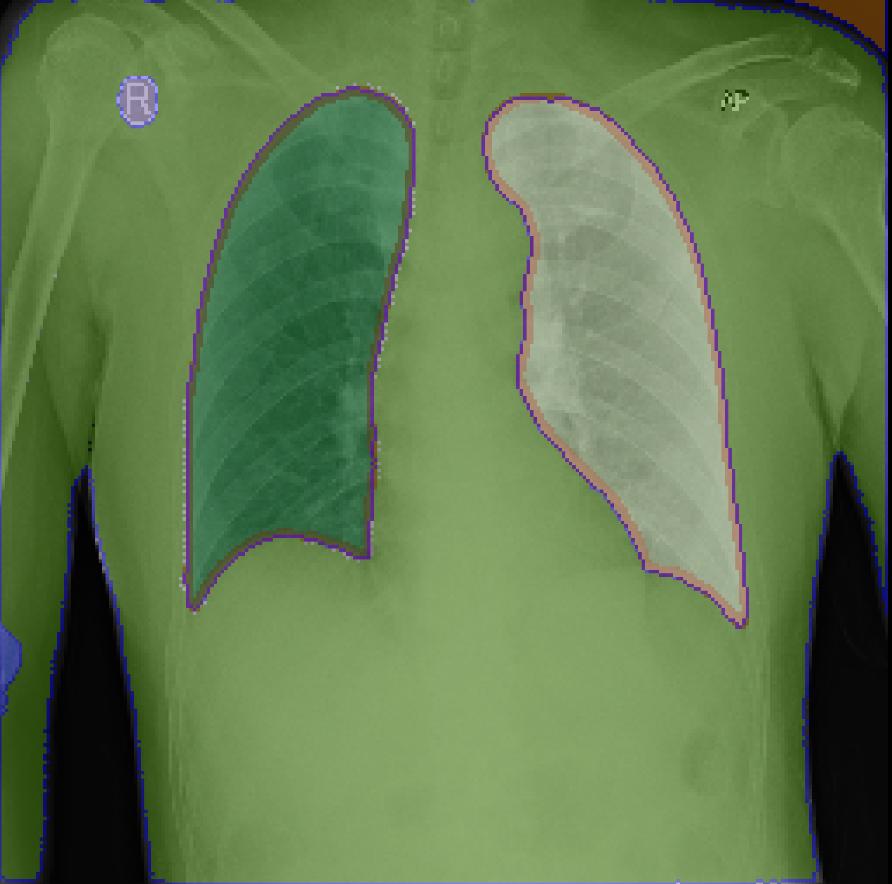

Figure 3: Sample outputs from various datasets showing regions of interest generated from SAM2.

Figure 3 shows the regions of interest generated by SAM2 for various datasets.